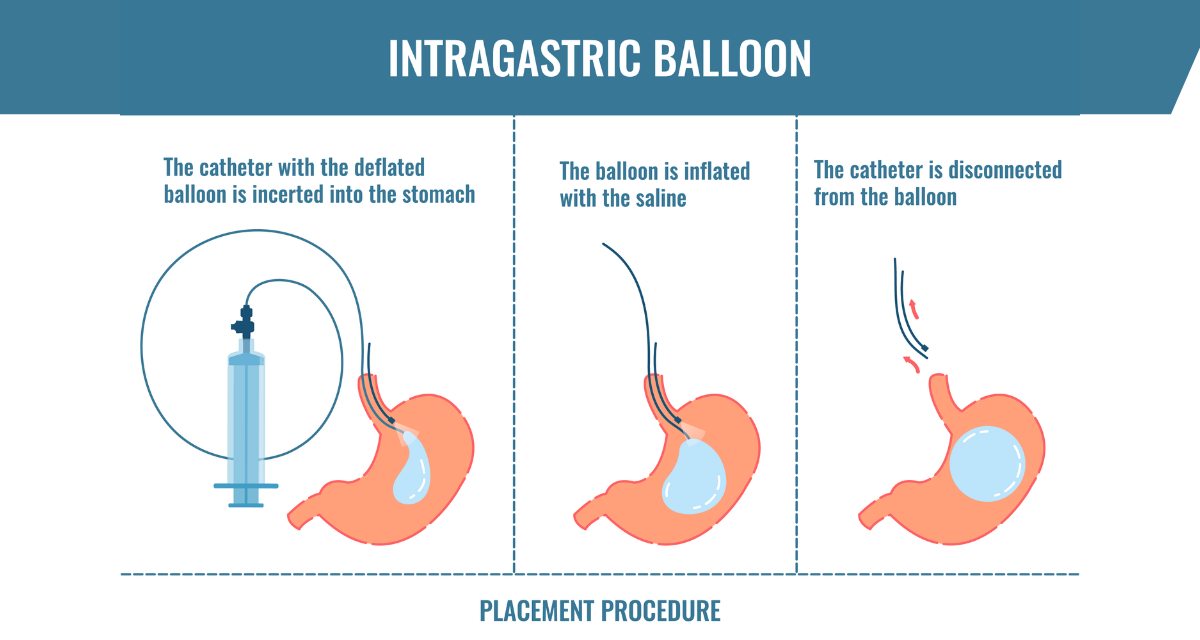

Баллон применяется эндоскопически, то есть без хирургического вмешательства. Поскольку пациент находится под наркозом, он ничего не чувствует во время процедуры и процедура завершается в среднем за 15 минут.

Перед наложением баллона эндоскопически оценивают пищевод, желудок и 12-перстную кишку и выявляют наличие противопоказаний к наложению баллона. После удаления эндоскопа у пациентов без противопоказаний баллон через рот и пищевод через специальный аппарат направляется в желудок. Далее, после выравнивания положения баллона в желудке повторным проведением эндоскопии, баллон раздувают путем введения в баллон с помощью специального эндоскопического аппарата физиологического раствора, окрашенного метиленовым синим.

Прежде всего, со временем дозу 400 мл физиологического раствора можно увеличивать в зависимости от переносимости пациента, и все эти процедуры выполняются эндоскопически. После процедуры пациент сразу просыпается и выписывается домой после пребывания в больнице примерно 1-2 часа.